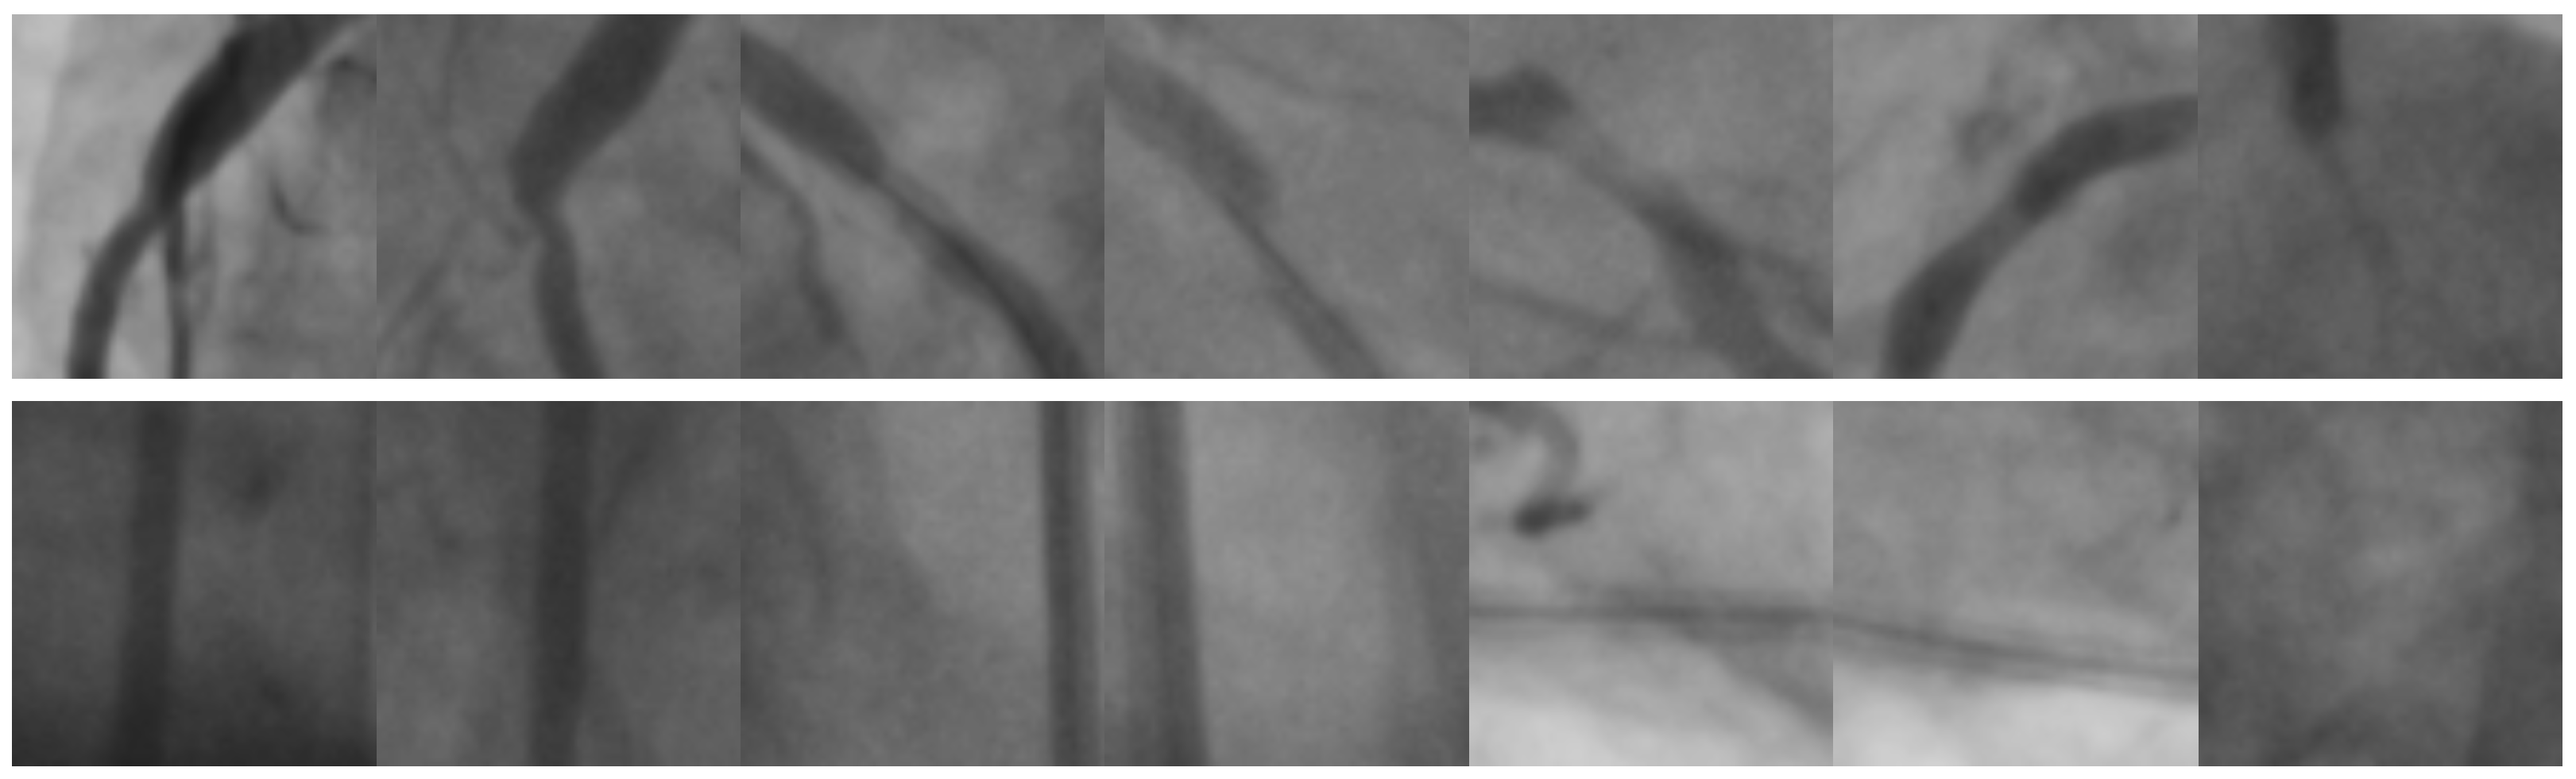

The second image database involves real and synthetic images corresponding to coronary stenosis regions [47]. The size of each image is pixels. Figure 10 illustrates a sample of 21 images containing natural and synthetic coronary regions of positive and negative stenosis cases.

Figure 10.

Image samples taken from the Antczak [47] image database. The first row contains natural images of coronary stenosis positive cases. The second row corresponds to synthetic images of positive cases. The third row corresponds to natural negative cases.